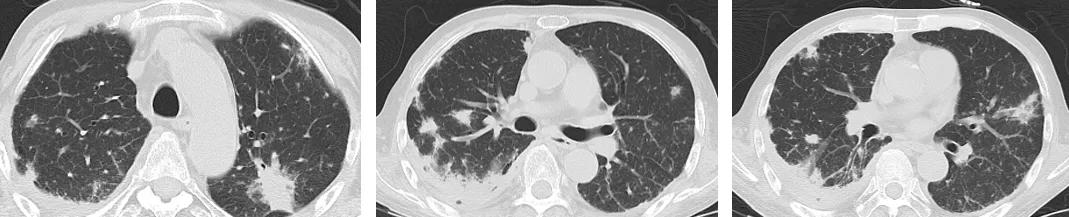

病例5:

男,52岁,溶血性贫血,激素治疗43天。

最初完全按照大叶型肺炎、细菌性肺炎治疗,没有明显效果。最后出现播散,用了机械通气,出现气胸等等。

病例6:

这位患者是急性单核细胞性白血病,化疗2个疗程后出现病症——发热、咳嗽,咳黄痰,很多人会因此想到细菌性肺炎。但事实上,做了气管镜、采样、活检,证实有大量的抗酸杆菌。肺组织活检证实是肉芽肿改变,最后确诊肺结核。

经过治疗以后明显吸收好转:

病例7:

患者是混合性结缔组织疾病,激素治疗6个月后出现发热,肺部病灶明显增多,两侧情况不一样,我们冒了很大风险给他做支气管肺泡灌洗,做刷检、做活检,刷检时也找到了抗酸杆菌,但活检的结果是:既有一般的结缔组织的肉芽肿性改变,同时也看到有结核的干酪样坏死。因为患者是在激素减量过程中出现的症状,所以我们考虑是既有结缔组织疾病,又合并了肺结核。

所以,在免疫功能低下、有基础疾病的人群当中,肺部出现病灶,有呼吸系统的症状或有发热,我们鉴别诊断的时候就不能想得那么简单,有时并不是一元论,有时是会出现 混合感染 ,结核可能合并普通细菌感染,也可以和真菌、巨细胞病毒合并呈现,因为在患者免疫功能低下时,很多条件致病菌可以同时出现,肺结核也不例外。